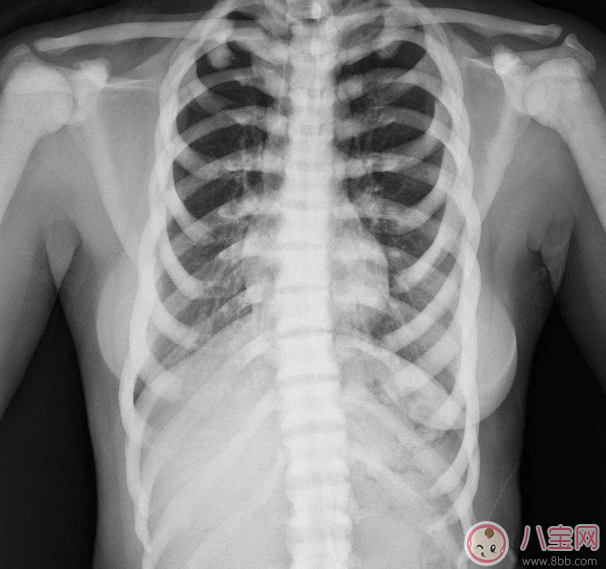

普通X線片即可確診。X線片上表現為:

①骨密度增高硬化廣泛均勻,骨小梁變粗、模糊,皮質增厚,髓腔狹窄,甚至消失;

③脊椎特征性改變呈夾心椎又名夾心蛋糕征,指椎體上下高密度而中間低密度,形如三明治樣改變;椎間隙一般不受影響;

石骨癥是一種少見的遺傳性疾病,臨床并不多見,容易出現漏診,診斷主要依靠X線的表現,有時需要通過生化和免疫學檢查結合CT、X線片才能確定其分型。同時要和某些化學元素中毒如:磷、鉛、氟中毒及成骨性骨轉移相鑒別。